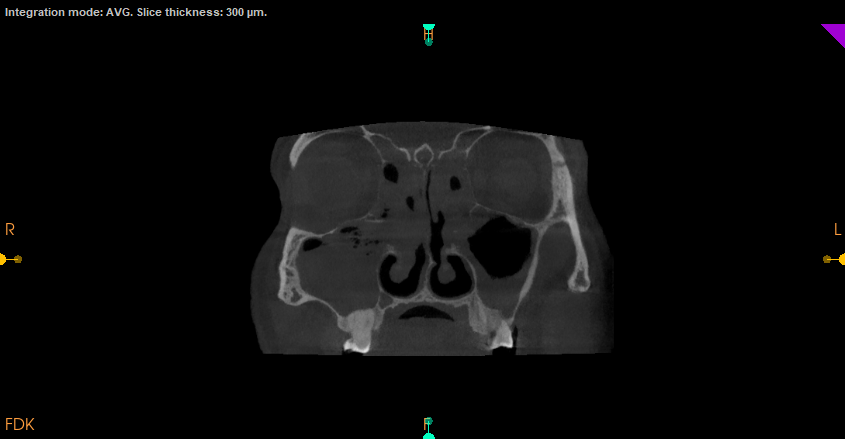

Cone Beam Computed Tomography (CBCT)

Special 3D imaging technique that provides detailed images of teeth, jaws, nerves, and surrounding structures. CBCT is quick, accurate, and offers 3 Dimensional knowledge compared to normal X-rays, ensuring better care for complex dental issues.

Accurate diagnostic features of various pathologies like cysts and tumors for better treatment planning

Endo Analysis of the tooth and related pathology

TMJ Assessment